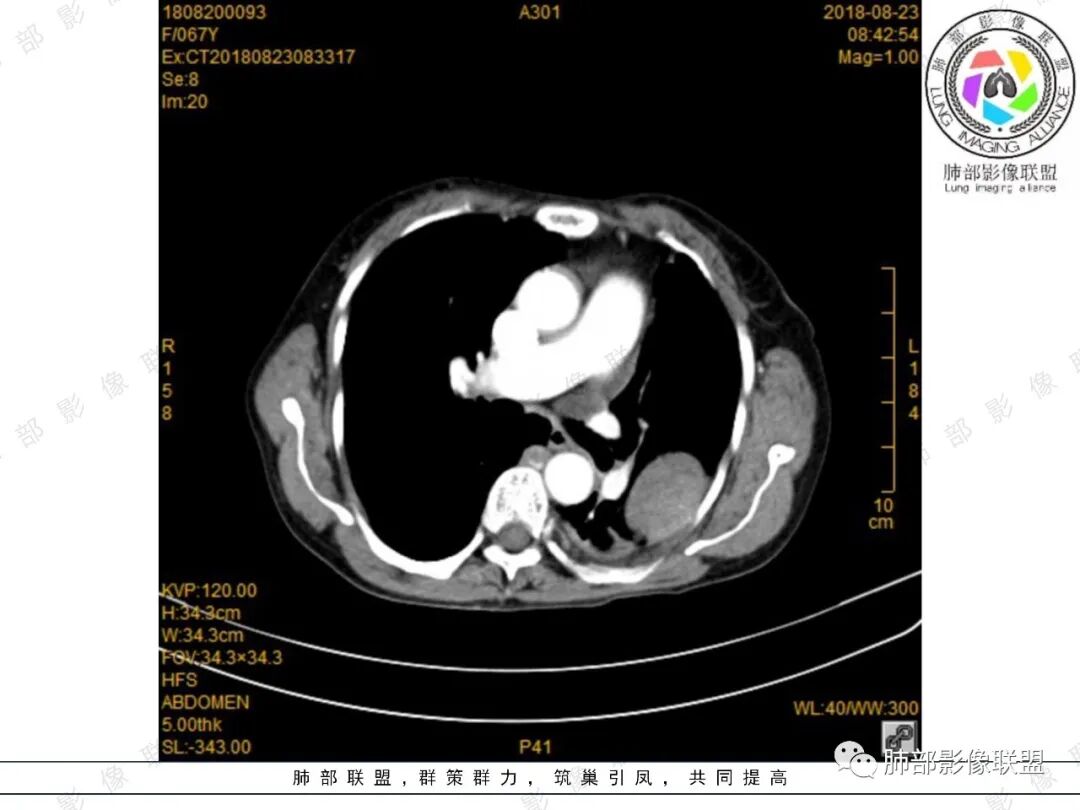

看图说话:左肺肿块,边缘光滑,密度不均匀,不均匀强化,胸腔少量积液,纵隔肿大淋巴结。脾脏增大,见肿块影,不均匀强化,一元论,考虑淋巴瘤,转移瘤。

大雄:定位肺外  无明显强化  有坏死或囊变   脾大

水晶石头:患者老年年女性,便血两天就诊,查NSE稍升高。胸部CT:左肺上叶类圆形肿块,边缘光滑,边界清楚,长轴与胸膜平行,与胸膜宽基底相连,内部密度较均匀,有低密度区,强化轻中度强化。综合考虑来源胸膜来源,胸膜孤立性纤维瘤可能大。鉴别其神经源性肿瘤。

月亮圆了!:左肺上叶胸膜下肿块,宽基底与胸膜相连,边缘清晰,局部肺组织受压,支气管显示不佳,平扫密度不均匀,增强后,可见轻度不均匀强化,纵隔光滑,无分叶,无毛刺,周围组织无牵拉,收缩,内部有不均匀低密度,脾脏明显肿大,脾内多发类圆形低密度影,增强后,轻度强化,有便血,考虑可能:1:淋巴瘤2:脾梗死。